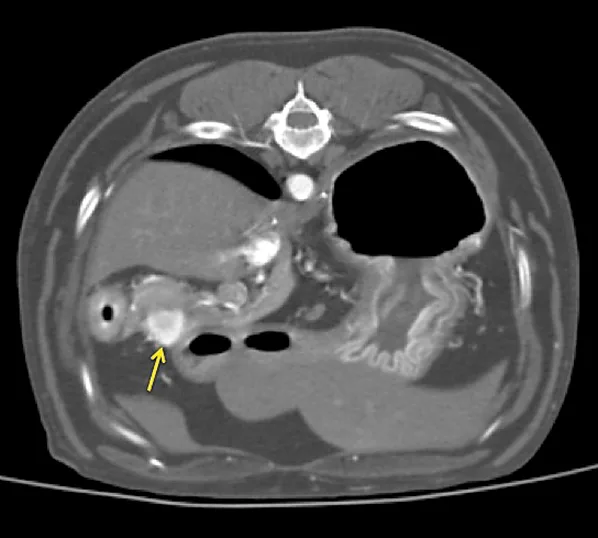

Figure 1 Sonographic image of the nodule at the base of the left lobe of the pancreas (outlined by red markers)

Additional diagnostics were pursued. Abdominal ultrasonography demonstrated an ill-defined and mildly hyperechoic 0.75 × 1.37-cm nodule at the base of the left lobe of the pancreas (Figure 1). Small, well-defined hyperechoic nodules were also found scattered throughout all liver lobes. Three-view thoracic radiographs revealed no significant abnormalities.